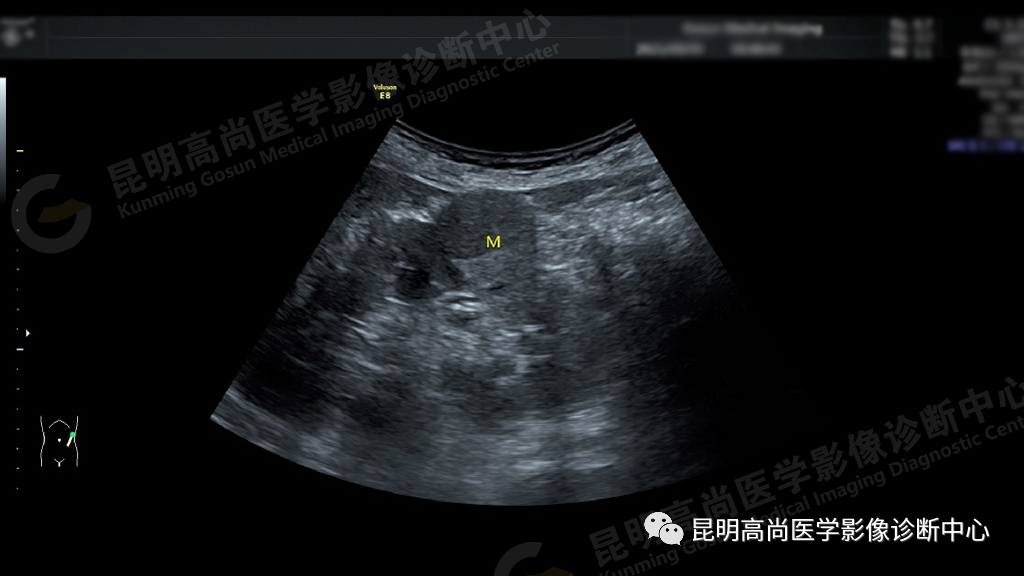

超声所见:左肾切面大小正常,形态失常,轮廓不规则局部突起,在左肾中部肾实质内可见一个大小约 25 mm×24 mm 肿块图像,形状呈圆形,内部为中等回声,分布不均质,边界清楚,似有包膜,后方回声无变化,彩色多昔勒显示:内可见丰富血流信号,肾门处未见肿大的淋巴结。

超声提示:左肾实质性占位病变,性质待查,建议进一步检查。